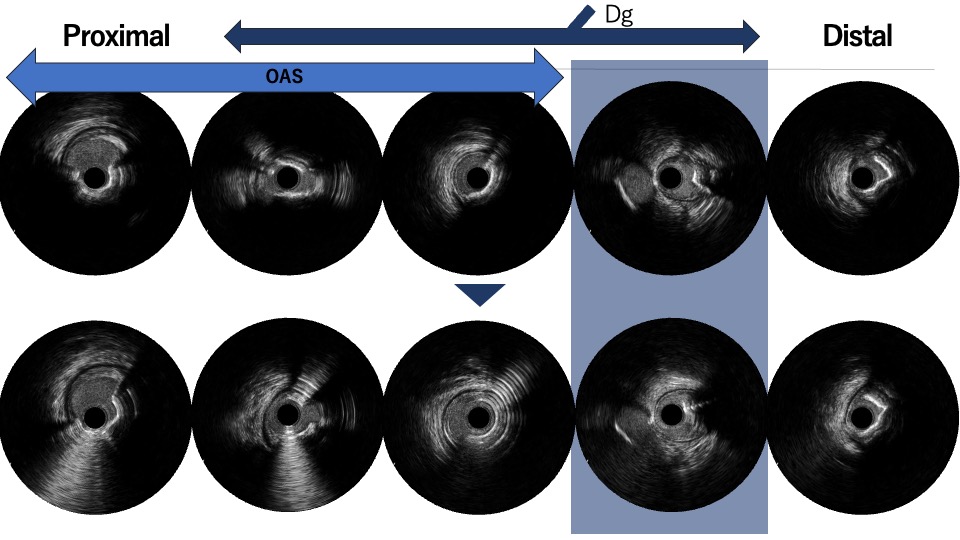

Coronary angiography via the radial approach showed a severe proximal LCx stenosis and a long, severe mid-LAD stenosis, while the RCA had no significant disease. IVUS of the LAD demonstrated diffuse calcification and an eccentric calcified plaque protruding from the septal side near the diagonal branch bifurcation. The guidewire was biased toward the diagonal branch, causing tenting of the relatively healthy wall at the most critical segment.

PCI was first performed for the LCx, using orbital atherectomy followed by cutting balloon predilatation and drug-coated balloon therapy with good angiographic result. One month later, PCI was attempted for the LAD lesion using a 8F system via right femoral approach. Intravascular ultrasound (IVUS) revealed a diffusely eccentric calcified plaque located on the septal side. While wire bias in the proximal segment was toward the calcified plaque, the distal segment showed tenting of the wire toward a plaque-free site on the diagonal branch side. At this point, we considered that debulking of the distal segment would be a high risk of vessel injury. We hypothesized that performing proximal segment debulking that had a favorable wire bias might shift the overall wire bias toward the septal side. Then Only proximal OAS was performed using pull-back ablation.Follow-up IVUS showed disappearance of distal tenting and favorable wire bias toward the calcified plaque. As a result, OAS was safely performed in the distal segment as well. Additional debulking of the residual calcified plaque was conducted with a 2.0 mm Rotablator. IVUS confirmed effective debulking without vessel injury in the area of concern. The entire lesion was then dilated with a CB; however, a dissection with hematoma occurred, and a drug-eluting stent (DES) was implanted. Final IVUS demonstrated acceptable stent expansion, and final angiography showed no residual stenosis or flow limitation.

In this diffusely calcified, eccentric LAD lesion, initial proximal debulking with orbital atherectomy intentionally modified wire bias and eliminated distal tenting, thereby enabling safe atherectomy in a high-risk distal segment. This case suggests that targeted proximal plaque modification can be a practical strategy for wire bias control in complex eccentric calcified disease, and underscores the importance of repeated IVUS assessment during such procedures.